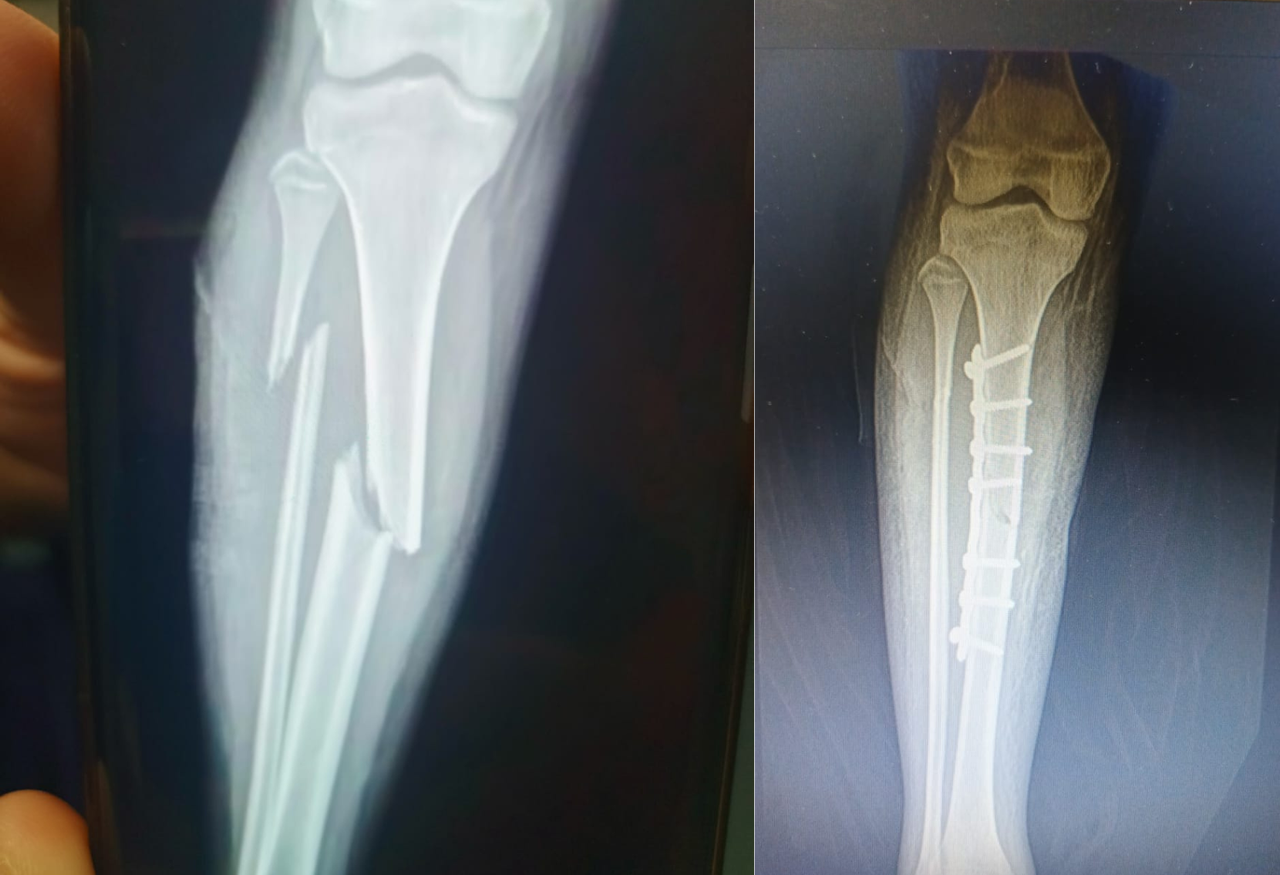

Fractura diafisaria de tibia y Peroné

Se realiza reducción abierta y estabilización con placa DCP y tornillos corticales